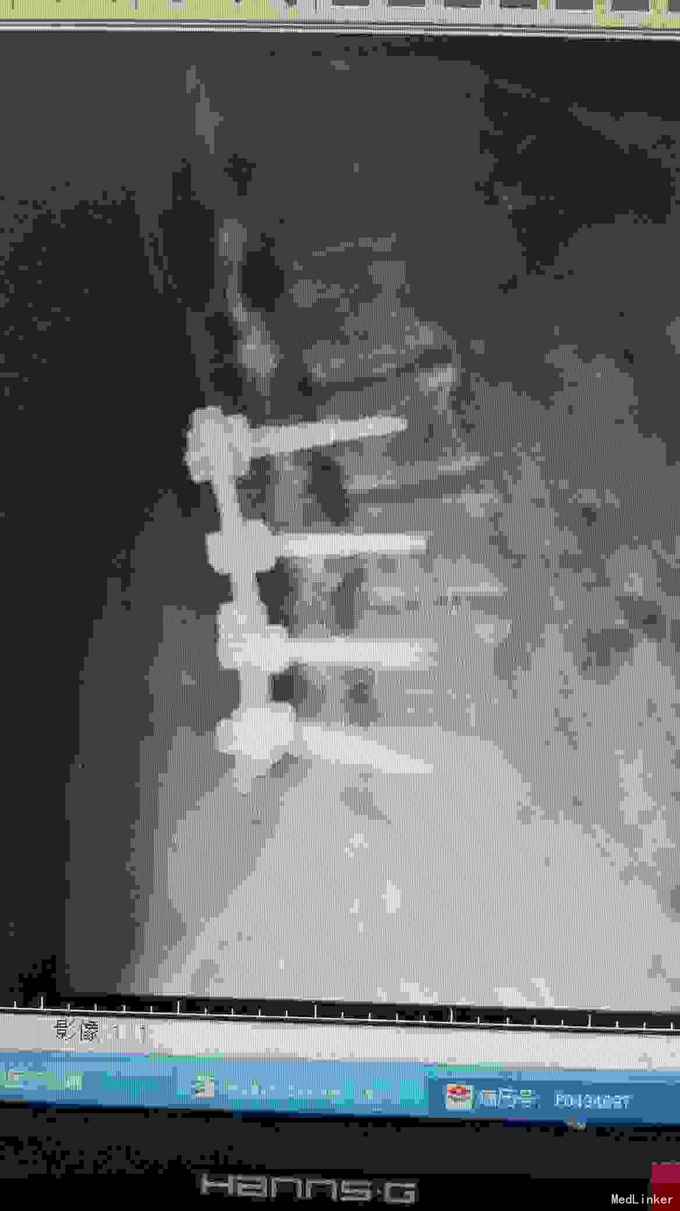

诊断腰椎间盘突出症,腰椎管狭窄症,腰椎退变性侧弯。 在全麻下行腰椎固定,减压,畸形矫正融合术。

患者术后腰疼及右下肢疼痛消失。